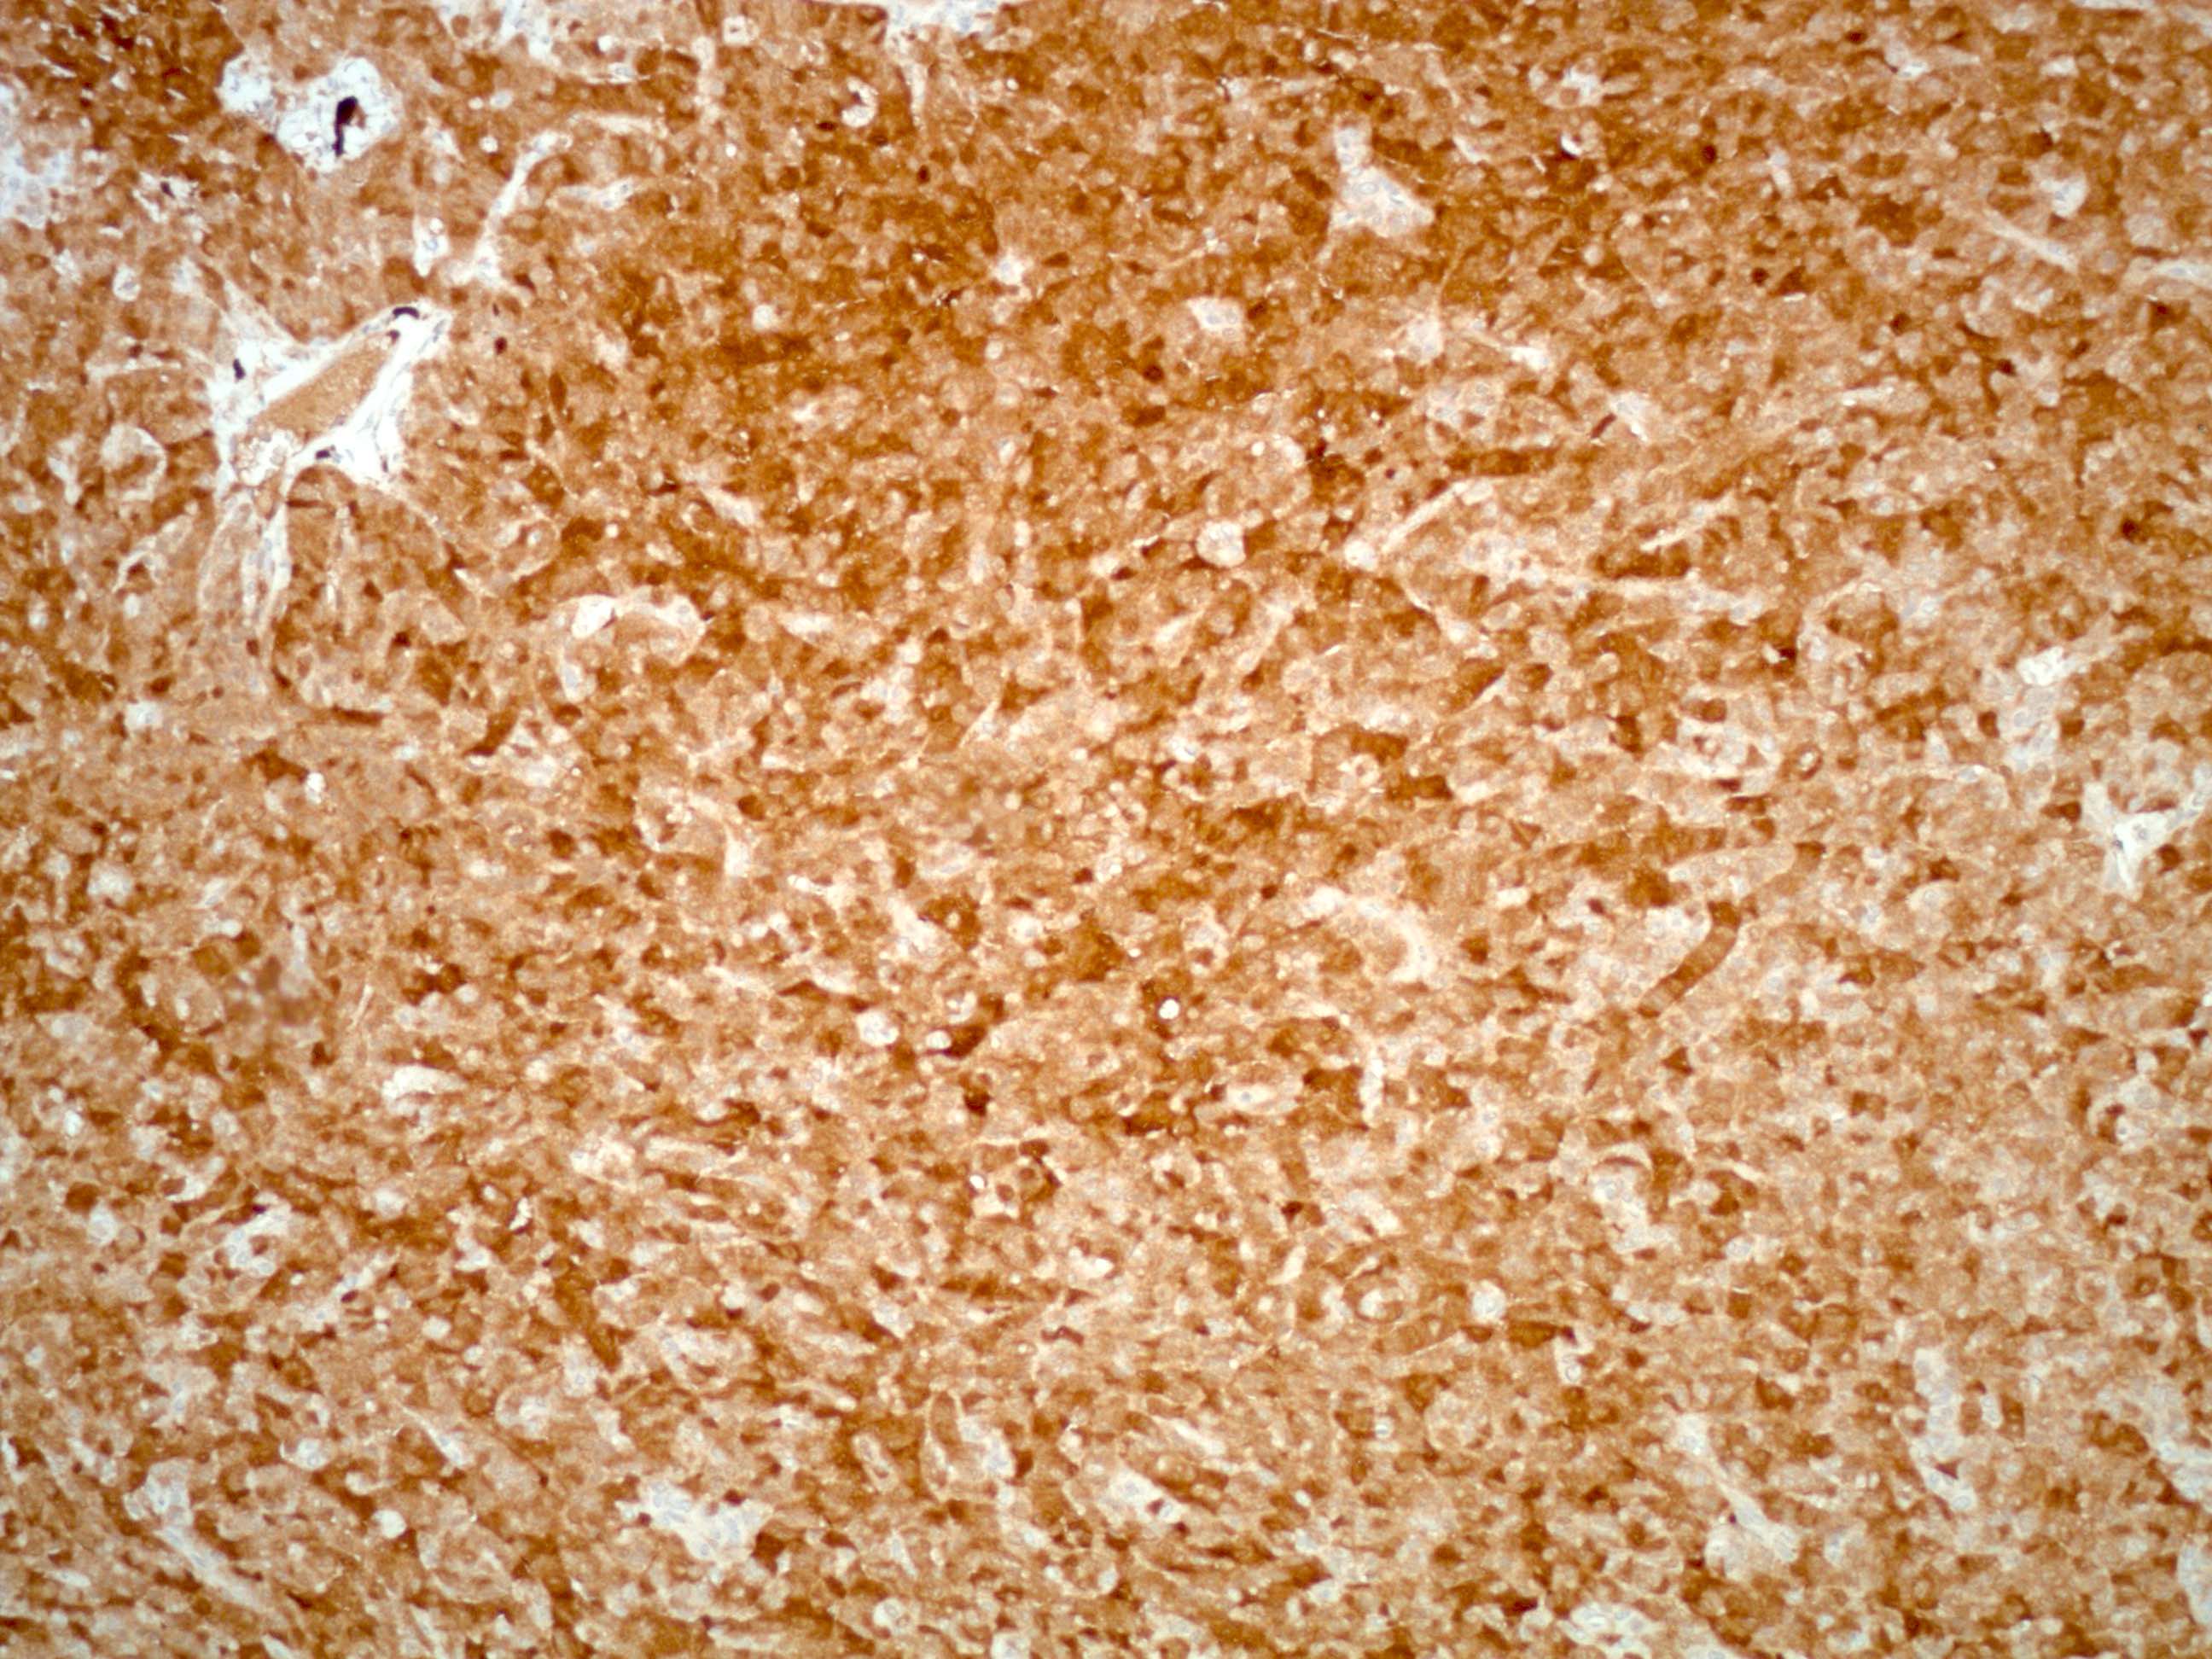

- FOXL2 mutation by immunohistochemistry or sequencing identified in > 95% (N Engl J Med 2009;360:2719)

- Immunohistochemical panel could include inhibin, calretinin, FOXL2, SF1, EMA and reticulin special stain

- FOXL2 immunostain is a sensitive (80%) and specific (99%) marker for sex cord stromal tumors (SCST), superior to α inhibin and calretinin and is positive in almost all SCST (98%) with FOXL2 mutation and a large number of those without mutation (67%); majority of adult GCTs (93%) are positive with FOXL2 stain and the immunostain cannot differentiate adult GCT from other SCSTs (Am J Surg Pathol 2011;35:484)

- SF1: most sensitive marker for this as well as most common sex cord stromal tumors (Am J Surg Pathol 2009;33:354)

- Inhibin A: more specific marker

- Calretinin (Am J Surg Pathol 2002;26:1477)

Contributed by Shabnam Zarei, M.D. and Sharon Bihlmeyer, M.D.

AFIP images